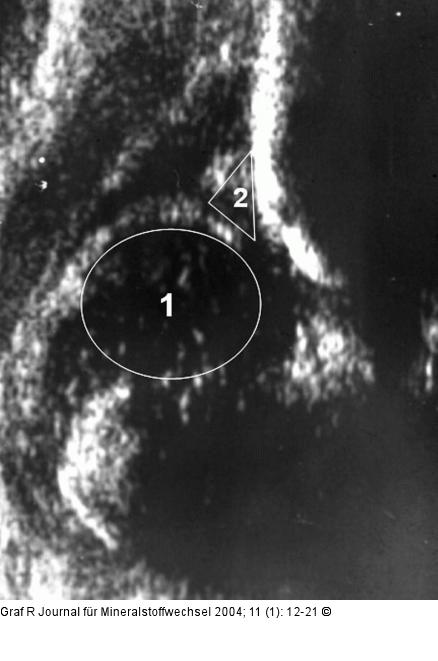

Abbildung 3: Hüftgelenk Hüftsonogramm eines luxierten Gelenkes vom Typ IIIa. Der Hüftkopf (1) ist deutlich aus der Pfanne herausgetreten, er hat das hyalin knorpelig präformierte Pfannendach (2) samt Labrum acetabulare nach cranial abgedrängt. |

Hüftsonogramm eines luxierten Gelenkes vom Typ IIIa. Der Hüftkopf (1) ist deutlich aus der Pfanne herausgetreten, er hat das hyalin knorpelig präformierte Pfannendach (2) samt Labrum acetabulare nach cranial abgedrängt. |